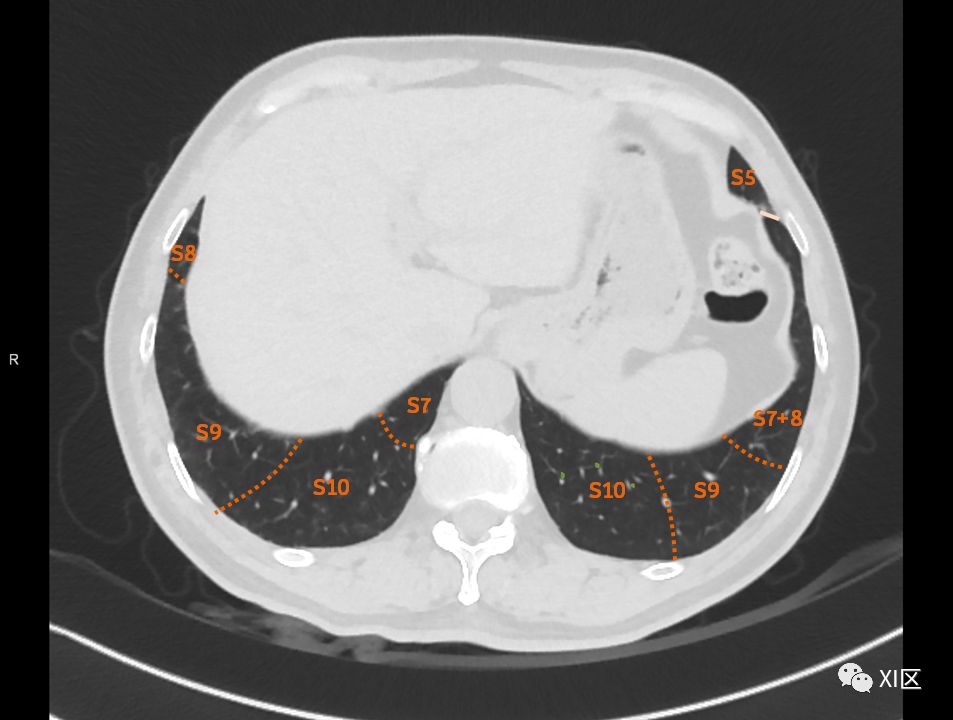

肺的断层分段示意图

在进行肺的分段时,可以上下观察浏览,沿着相应气管的走形可以更容易准确地进行分段。